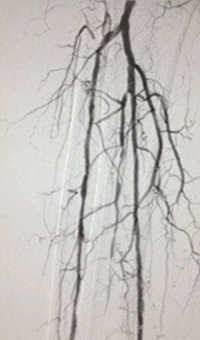

Acute DVT left lower extremity revascularization

47 year old male presented with leg swelling ~2 weeks.

Procedural steps

• Power Pulse delivery of 10mg tPA followed by

• 20 minute dwell time

• Total runtime was 300 seconds

Acute DVT Left Lower Extremity Revascularization pre-treatment angio.

Acute Iliofemoral thrombus pre-treatment

IVC Filter placed (left image)

Acute DVT Left Lower Extremity Revascularization post-treatment.

Post ZelanteDVT  pharmacomechanical thrombectomy

Case images courtesy of David Wilson M.D. – Harbin Clinic, Rome, Georgia – December 19, 2015